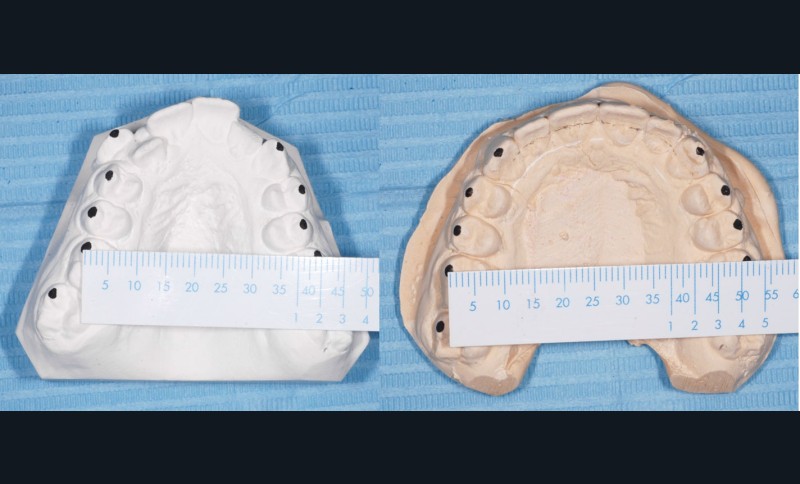

Sans aucun appareillage d’expansion, le maxillaire a été transformé et semble avoir été soumis à une disjonction (fig. 30).

Les moulages avant-après montrent une augmentation du sens transversal de 10 mm au niveau des 1re et 2e prémolaires (fig. 31).